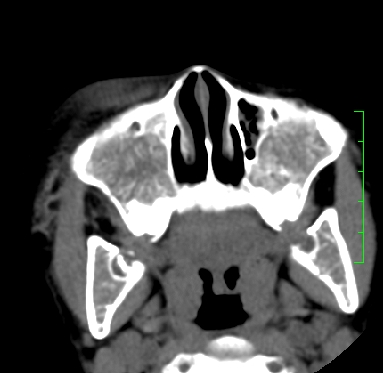

标题: PED1889:上颌窦病变

m,10y,外伤做ct

骨纤?

支持;骨纤,有皮肤色素沉着,性早熟时为albright综合征。

霉菌性鼻窦炎

骨化性纤维瘤可能性大。(与骨纤的鉴别:常见于面颅骨,多骨发病)